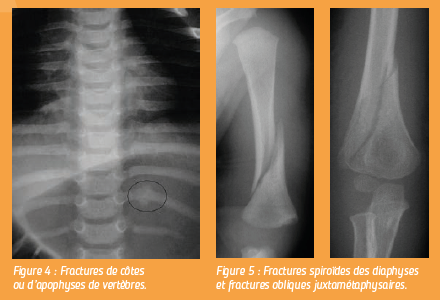

Ces fractures sont difficiles à identifier et nécessitent une technique rigoureuse et un oeil expert. Les fractures de côtes ou d’apophyses de vertèbres sont pratiquement synonymes d’enfant battu en dehors d’un polytraumatisme connu.

Les fractures spiroïdes des diaphyses et les fractures obliques juxtamétaphysaires du jeune enfant doivent être considérées comme suspectes en l’absence de corrélation précise avec un traumatisme.